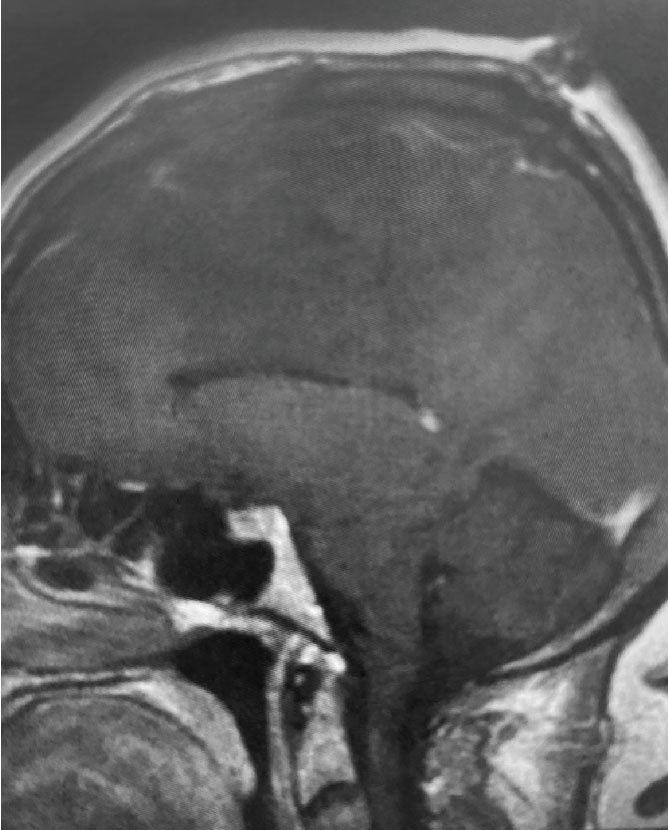

Fig 1. B) Pre-operative, sagittal post-contrast MRI.

This is a 55 year old right-handed woman who was having progressive balance problems. MRI with and without contrast demonstrated a 7 cm partly cystic meningioma involving the left frontal convexity and falx, and encasing the superior sagittal sinus. There was also tumor involvement of part of the convexity skull.

Meningiomas that compress the motor strip: This meningioma was clearly compressing the left motor strip significantly, likely explaining the patient’s balance problems. That having been said, these tumors often have very distinct borders with the normal brain, and can be removed without harming the underlying motor strip.